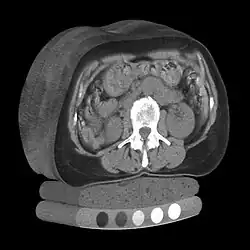

Quantitative computed tomography (QCT) is a medical technique that measures bone mineral density (BMD) using a standard X-ray computed tomography (CT) scanner with a calibration standard to convert Hounsfield units (HU) of the CT image to bone mineral density values.[1] Quantitative CT scans are primarily used to evaluate bone mineral density at the lumbar spine and hip.

In general, solid phantoms placed in a pad under the patient during CT image acquisition are used for calibration. These phantoms contain materials that represent a number of different equivalent bone mineral densities. Usually either calcium hydroxyapatite (CaHAP) or potassium phosphate (K2HPO4) are used as the reference standard.[2]

QCT scan protocols are low-dose and can limit the amount of radiation exposure to between 200-400μSv for a spine exam[6] This is comparable to a set of mammograms and typically substantially less than a standard CT exam. Using other non-IV contrast abdominal or pelvic scans such as a Virtual Colonography studies, the QCT exam can be performed without requiring any further image acquisition or consequent radiation dose to the patient.[7]

Dual use of CT images

Several studies have shown that bone density may be measured by QCT using CT images that were ordered for other purposes. Using pre-existing images, including CT colonography exams,[14] QCT allows for bone density screening without submitting the patient to any additional radiation exposure. The feasibility of using routine abdominal contrast-enhanced CT scans for the evaluation of bone density by QCT has also been demonstrated.[15]